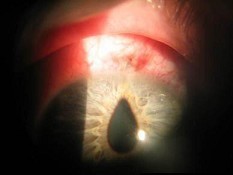

男性,25岁,左眼撞到摩托车扶手,裂隙灯检查如图,该患者的手术指征()

-

诊断晶状体半脱位(如图)的体征有()